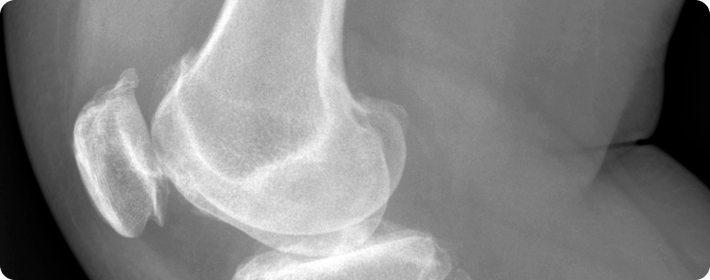

인공관절 수술

손상된 관절을 인공 관절로 교체하는 수술입니다. 전치환술, 부분치환술, 재치환술 등 다양한 방법으로 시행되며 각 관절의 상태에 따라 선택됩니다.